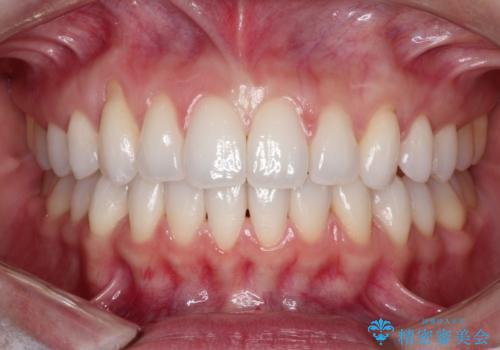

八重歯をマウスピース矯正で治療し、レーザーホワイトニングを行った症例

- 主訴:「右上犬歯を引っ込めて、歯並びをキレイにしたい」

右上の八重歯を気にされてご来院されました。結婚式を控えていたため挙式にまでに可能な限りキレイにしたいとのことでした。

また、ホワイトニングも一緒にご希望されたため、挙式のタイミングに合わせてレーザーホワイトニングを施術させていただきました。

右上の犬歯の歯茎は矯正前から退縮を起こしていましたが、矯正後もその退縮に関しては変化がありませんでした。今回は患者様が歯肉退縮に関しては治療をご希望ではありませんでしたが、当院ではこのように歯茎が下がり露出した根面を、歯茎を移植することでカバーし見た目を改善する手術を行っています。